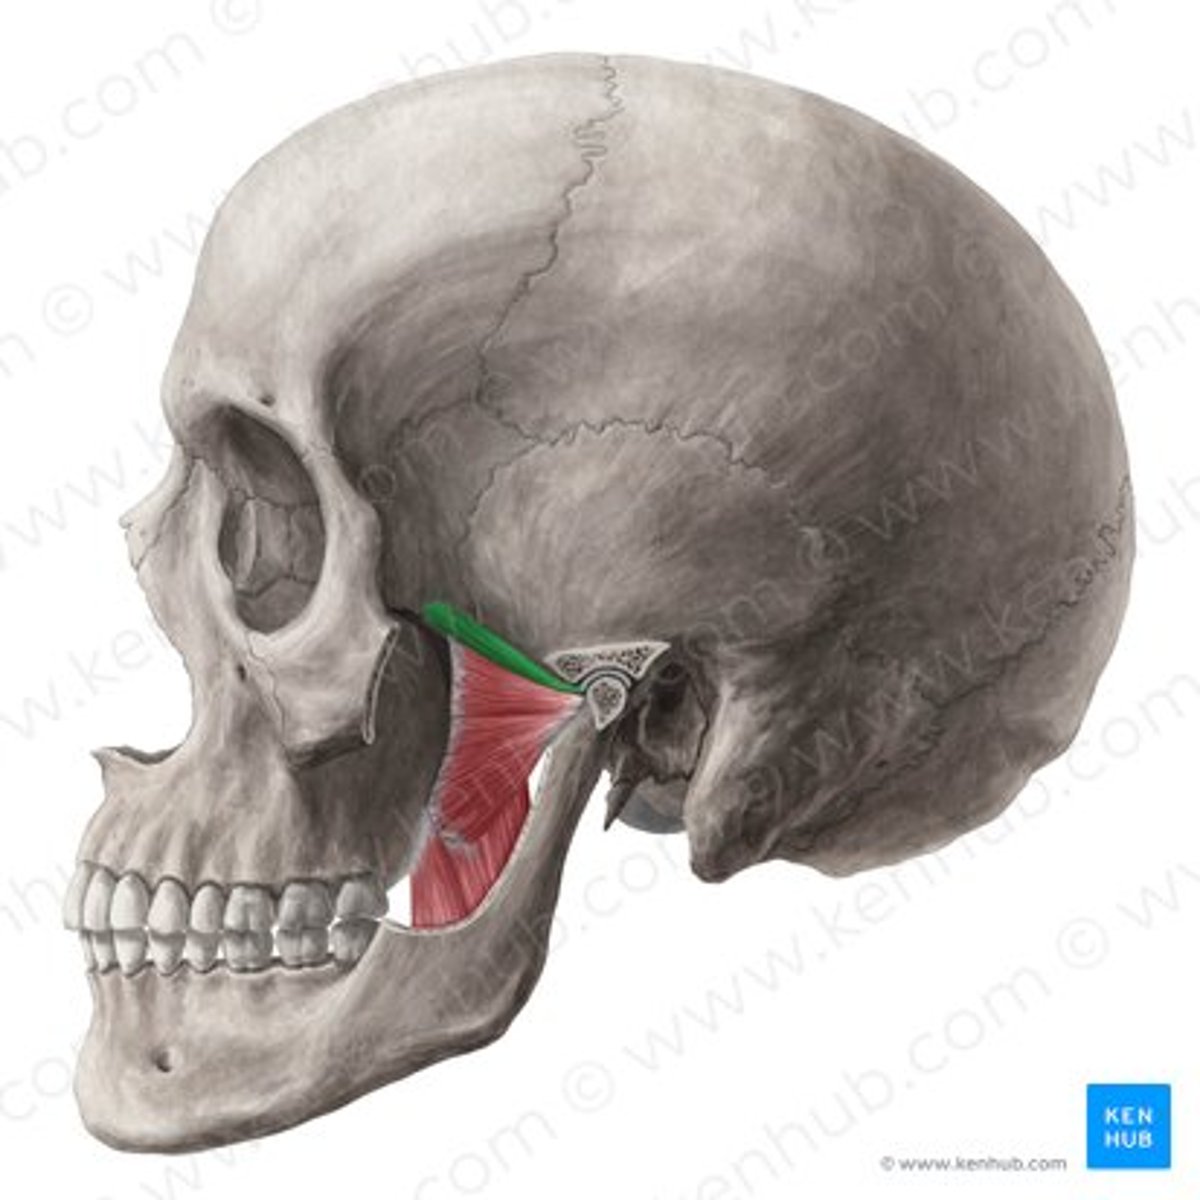

lateral pterygoid

lateral pterygoid, superior part

lateral pterygoid, inferior part

articular tubercle

head of mandible

articular disk

joint capsule